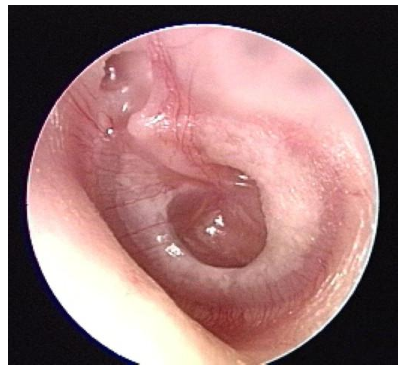

Bulging TM

due to infection or pus in middle ear

Bubbles

Yellow fluid in bubbly ear means what?

Could be infected